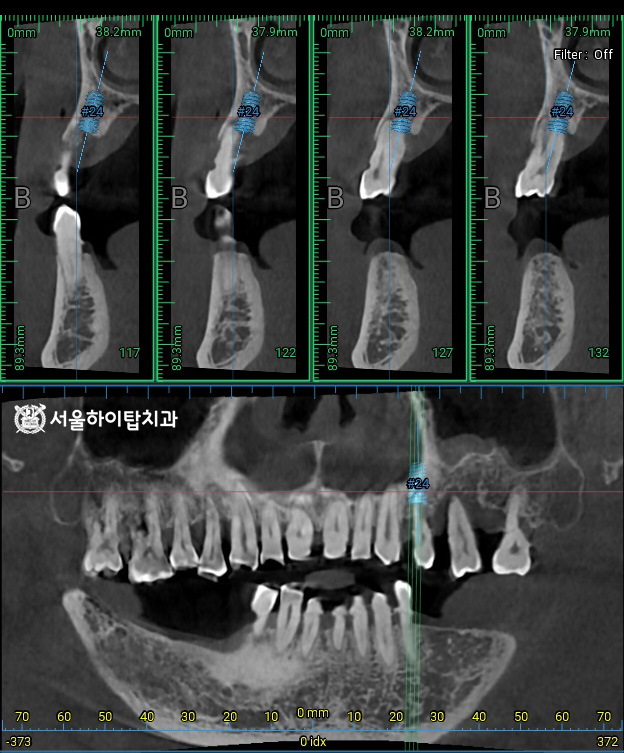

1. 초진

초진 파노라마 엑스레이입니다.

주안동 치과 에서는 전체적으로

뼈의 높이가 낮아진 것을

한눈에 확인할 수 있습니다.

특히 아래턱 양쪽 구치부는

이미 어금니가 모두 상실되었으며,

위턱은 사진 기준 오른쪽 구치부에

심한 염증이 관찰됩니다.

이로 인해 치아들이 마치 공중에 떠 있는 듯한

‘Floating Tooth’ 모습으로 나타나고 있습니다.

즉, 일부 자연치는

주변 뼈 지지가 거의 없기 때문에

장기적인 유지가 어려운 상태,

즉 Hopeless Tooth 임을 시사합니다.

2. 계획 수립 및 정밀 CT 촬영

이와 함께, CT 촬영을 통해

픽스처가 식립될 위치를

사전에 시뮬레이션할 수 있습니다.

주안동 치과 에서는 이를 통해

잔존 치조골의 높이, 밀도, 두께,

해부학 구조물 등을 면밀히 분석하고,

시술 과정과 보철 설계를 정확하게

계획할 수 있다고 설명드립니다.